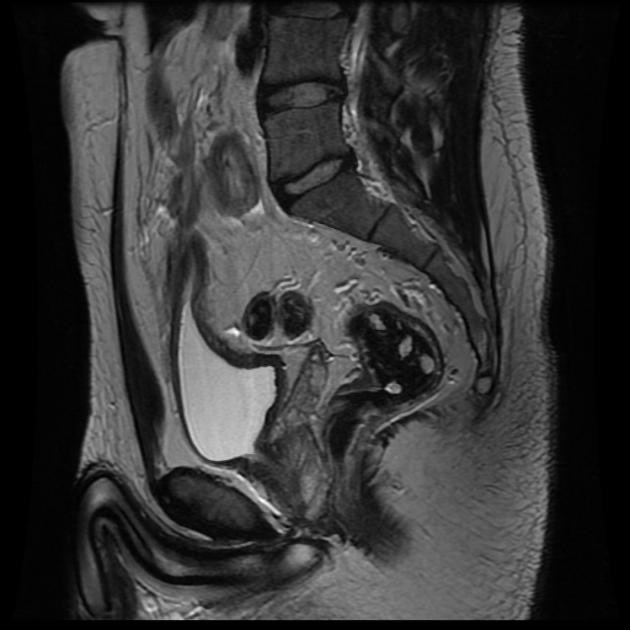

2️⃣ الأشعة

✳️ أشعة مقطعية

✳️ أشعة الرنين المغناطيسي

تطلب لتقييم الاجزاء المصابة في الجهاز الهضمي والكشف عن وجود اي نواسير في مرض الكرون